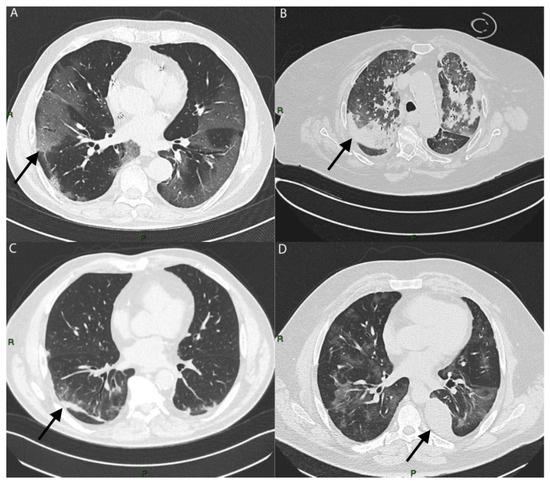

To estimate the involvement of lung lesions, we used a semi-quantitative CT-score system that ranged from 0 to 5 points for each lobe (Figure 4).

Figure 4. Coronal TC image of two COVID-19 patients: (A) patient with low CT score (5/25); (B) patient with high CT score (24/25).